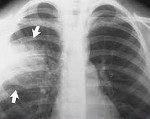

Полное диагностическое обследование при подозрении на внутрибольничную пневмонию строится на сочетании клинических, физикальных, инструментальных (рентгенография легких, КТ грудной клетки), лабораторных методов (ОАК, биохимический и газовый состав крови, бакпосев мокроты).

Для выставления соответствующего диагноза пульмонологи руководствуются рекомендуемыми критериями, включающими в себя: лихорадку выше 38,3°С, усиление бронхиальной секреции, гнойный характер мокроты или бронхиального секрета, кашель, тахипноэ, бронхиальное дыхание, влажные хрипы, инспираторную крепитацию. Факт внутрибольничной пневмонии подтверждается рентгенологическими признаками (появлением свежих инфильтратов в легочной ткани) и лабораторными данными (лейкоцитозом 12,0х109/л, палочкоядерным сдвигом 10%, артериальной гипоксемией Ра02.